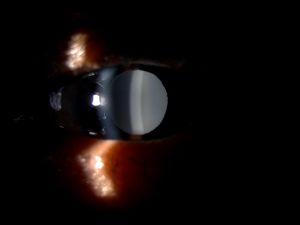

Clinical Diagnosis

The key to diagnosis is careful slit lamp examination in high magnification paying special attention to the IOL optic surfaces for signs of granularity or opacification. Slit lamp photography helps to monitor progression. Visual acuity and contrast sensitivity are reduced in IOL opacification cases.